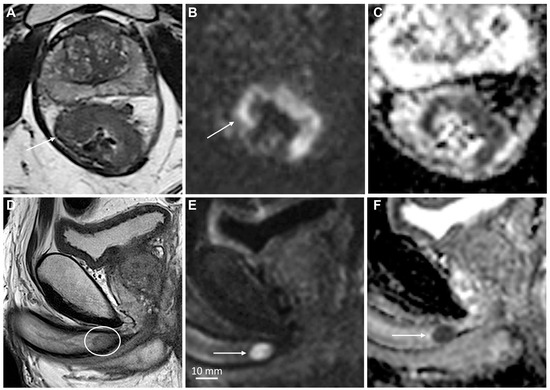

3.3. Role of MRI in Staging of Penile Cancer